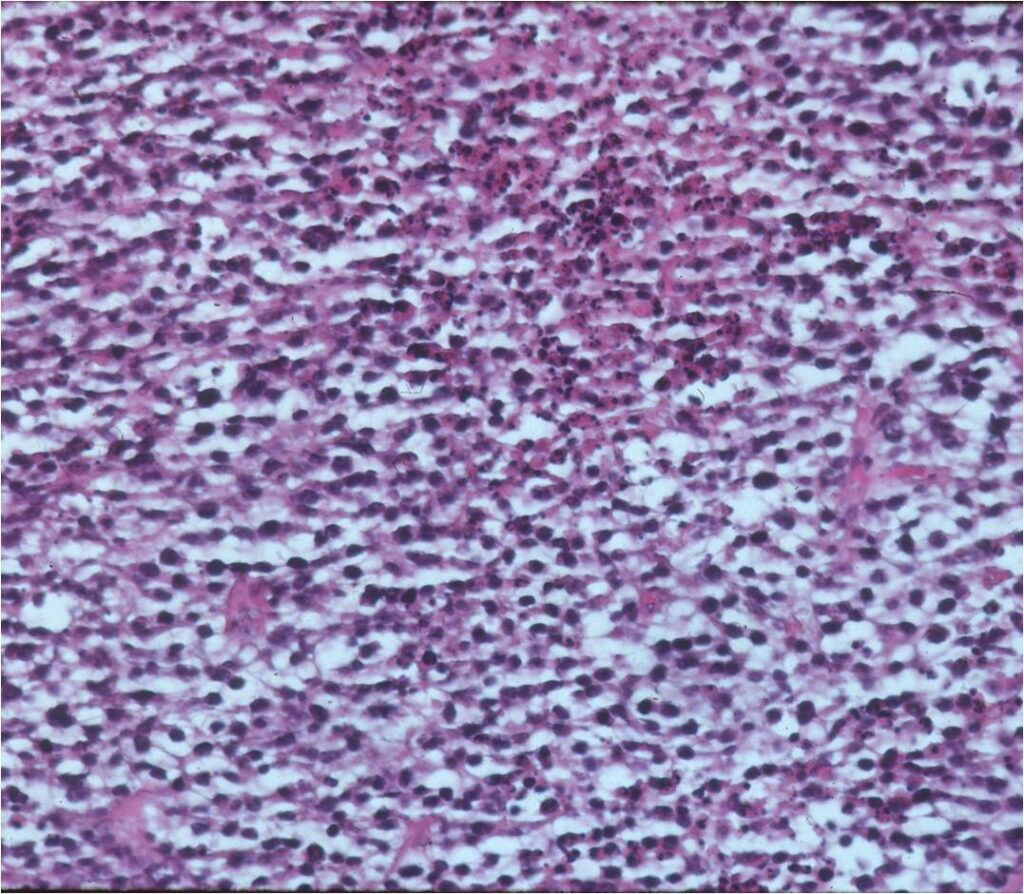

Microscopic Pathology

- Diffuse growth pattern

- Mixture of small lymphocytic cells and larger histiocytic components (Large Malignant B Cells in most cases)

- Cells and no matrix

- Nuclei

- Vary in shape and size

- Grooved vesicular nuclei

- Prominant nucleoli

- Cytoplasmic glycogen is absent

- Complex reticulin framework

- Prominent fibroblastic component

- CD5 and Leukocyte Common Antigen Positive

- CD3+ and CD45+ for B Cell Lymphoma; CD3+ for Rare T-Cell